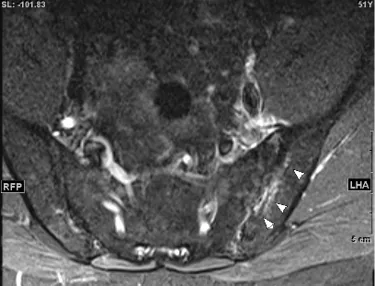

中年男性に発症した、単関節炎とその周囲炎(Psoriatic onycho-pachydermo periostitis:POPP)。血清反応陰性で、尿酸値は正常。尋常性乾癬あり、足趾に爪病変をみとめた。また詳細な病歴聴取にて2週間前から炎症性腰背部痛を認めたため、脊椎の側面および骨盤正面単純X線検査を行うも異常なし。その後仙腸関節および全脊椎MRIを施行し(図3a:T2FS, b:T2FS, c:T1)、左仙腸関節に骨髄浮腫の所見を数スライスにわたりみとめ、X線基準を満たさない体軸性脊椎関節炎(体軸性乾癬性関節炎)と診断した。

図3a,b,c 仙腸関節MRI